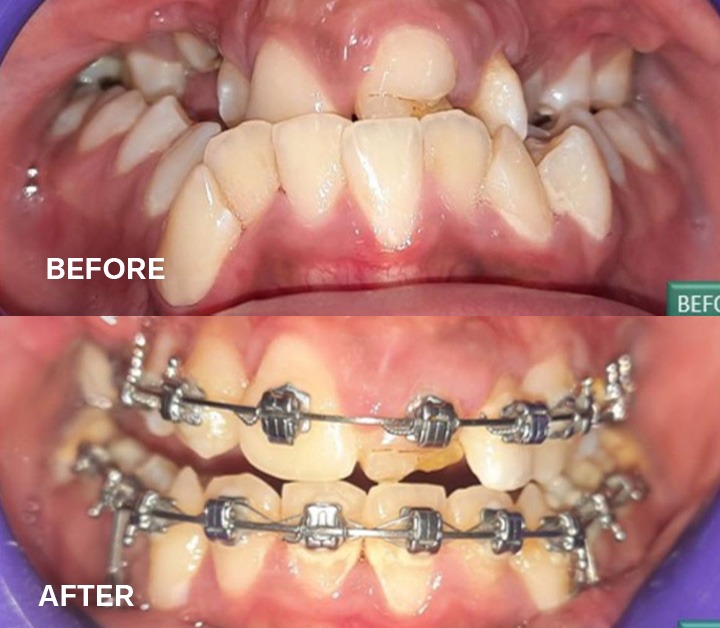

Damon self-ligation for non- non-extraction treatment plan

What Are Self-Ligation Brackets?

Self-ligation brackets are advanced orthodontic brackets designed with an additional wall that functions as a door. This door can be easily locked and unlocked, eliminating the need for traditional elastic ties. At Richardson Face Hospital, we offer the best orthodontics treatment in Bangalore, ensuring efficient and effective orthodontic care with these advanced brackets.

What Are Damon Brackets?

Damon brackets, developed by Dwight Damon, are self-ligation brackets paired with high-grade copper NiTi wires. These brackets efficiently treat complicated orthodontic cases in less time. At Richardson Face Hospital, known for the best orthodontics treatment in Bangalore, we use Damon braces to deliver excellent results.

Difference Between Damon Braces and Traditional Braces

Damon braces differ significantly from traditional braces in design and material, offering several advantages:

• Fewer appointments: Reduced need for frequent adjustments.

• Shorter visit times: Streamlined processes during each appointment.

• Less discomfort: Minimal force application over an extended period.

• Improved hygiene: No elastic ties to trap food or bacteria.

They are particularly effective for children with poor oral hygiene and cases involving severe teeth overlap. This is why they are a core part of the best orthodontics treatment in Bangalore.